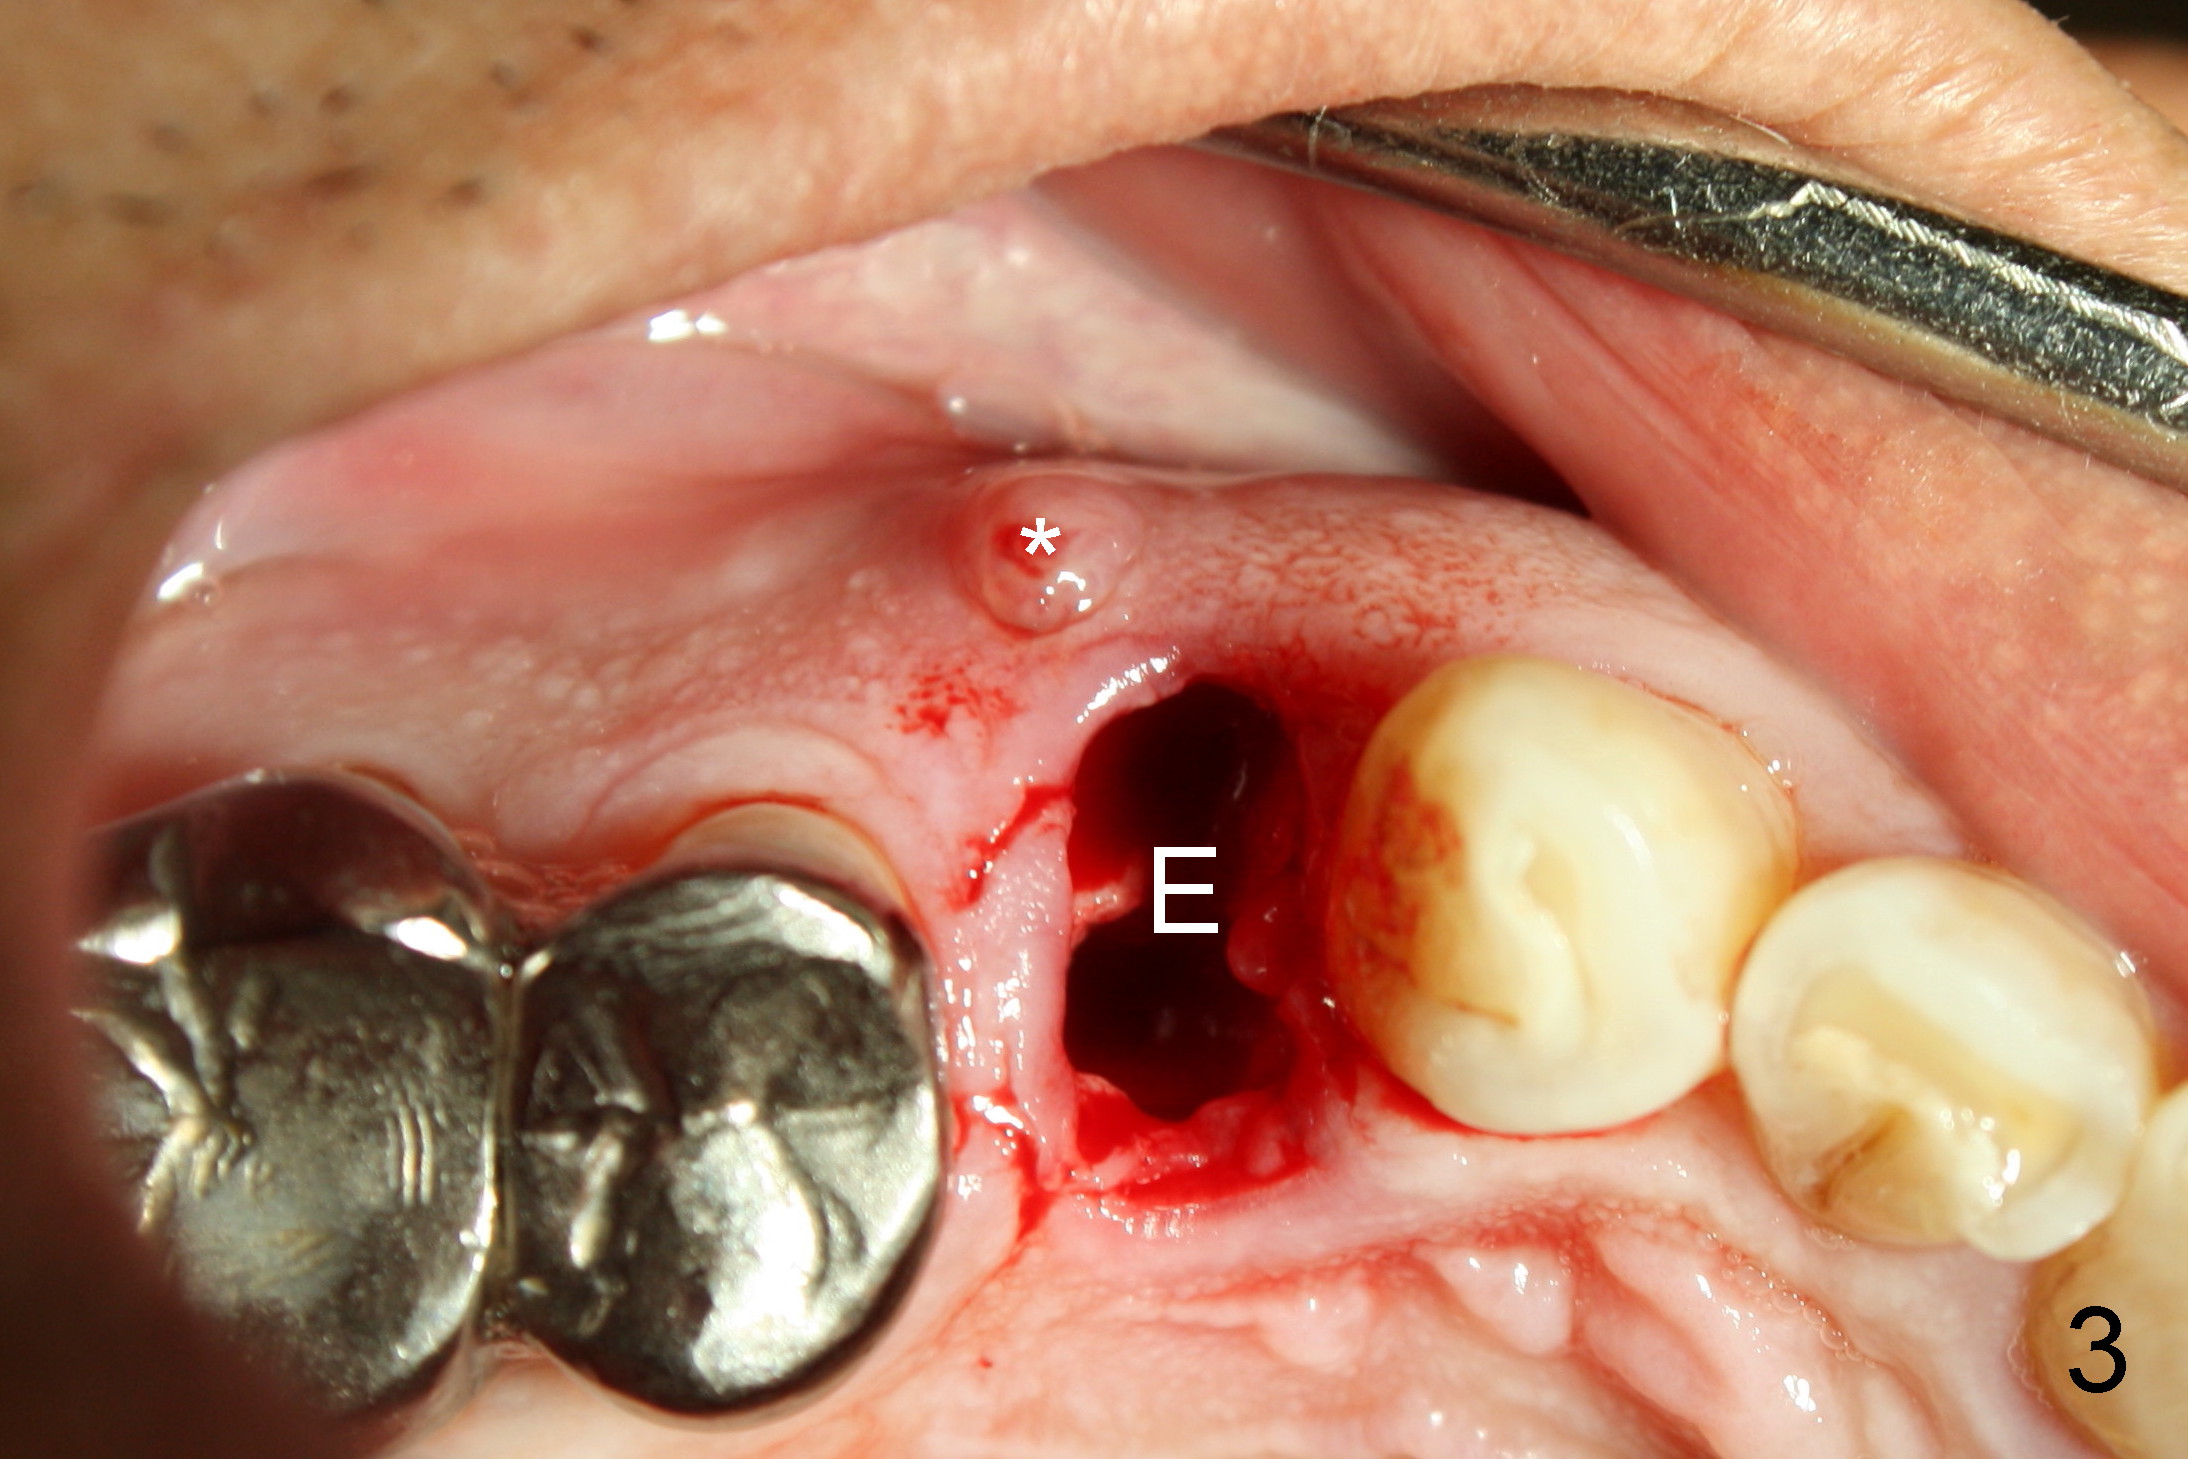

A 68-year-old man has pain and swelling associated with the tooth #5 (Fig.1). The fistula (*) is connected to the periapical radiolucency using a gutta percha (Fig.2 <). There are deep pockets distobuccal and lingual. The lingual root is found to have oblique fracture upon extraction. The distobuccal plate perforates (Fig.3). Collagen plug is placed. The buccal plate is concave (Fig.4) and socket density is low 2.5 months post extraction. Three months post extraction a 4.5x8 mm Bicon implant is placed after reamer and osteotome osteotomy (Fig.6). Bone density around the implant appears to increase 5 months post placement (Fig.7). Porcelain-fused-to-metal crown is cemented 2 weeks later. Bucco-occlusal porcelain chips 2 months post cementation. The patient decides to redo the crown. PA is taken before crown removal (Fig.8: 3 year 10 months post cementation). When a straight abutment is removed (Fig.9 A), a 15° angled abutment has to be used (Fig.10 red) for restoration.